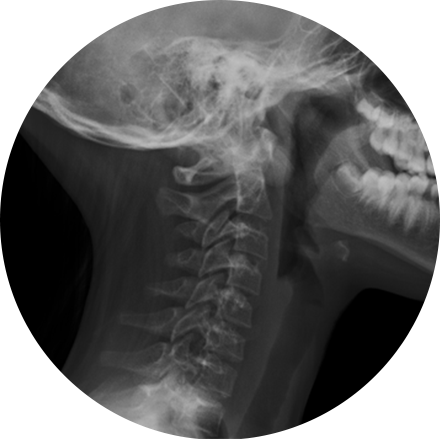

Digital X-ray

X-ray is the oldest and most economical form of medical imaging. During the procedure, radiation passes through the body onto “film” (now digitized and displayed on a computer screen). In neuroimaging, spinal X-rays are used to assess for the degree of spinal motion with flexion or extension.